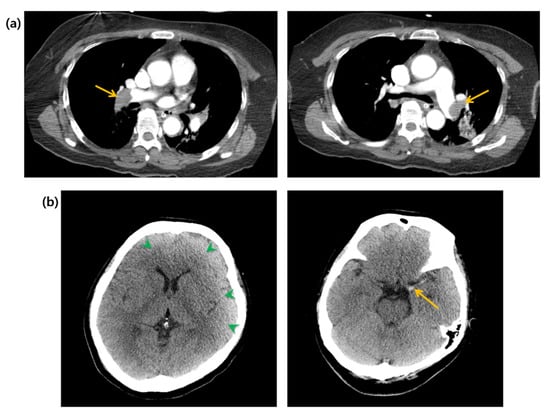

Figure 2.

(a) Computed tomography of the chest. Arrows indicate massive pulmonary embolisms. (b) Computed tomography of the brain. Green arrowheads indicate widely decreased gray matter density. Yellow arrow indicates hyperdense middle cerebral artery sign.

A 58-year-old woman with an unremarkable medical history visited the emergency department (ED) for worsening dizziness and dyspnea, noted one day before. The patient was alert and had normal peripheral oxygen saturation (SpO2) when the paramedics arrived. However, her mental state and oxygen saturation level declined during transport to the hospital. She had an SpO2 of 83% despite receiving 100% oxygen supplementation through a face mask with a reserve bag. The blood pressure was not measured due to a weak pulse. The patient was drowsy upon arrival at the ED. Cardiac arrest with pulseless electrical activity occurred after five minutes, and spontaneous circulation was restored after two minutes of cardiopulmonary resuscitation. A computed tomography (CT) of the brain, chest, and abdomen–pelvis (AP) was taken two hours after arrival. The AP-CT revealed an 8 × 11 cm saccular aneurysm involving the left and right renal veins at the infrahepatic level of the IVC (Figure 1). The chest CT revealed massive pulmonary embolisms involving both distal main pulmonary arteries (Figure 2a). A hyperdense middle cerebral artery (MCA) sign indicating thrombosis of the M1 MCA segment and widely decreased gray matter densities in the left hemisphere and right frontal lobe were detected on the brain CT (Figure 2b) [5]. A tissue plasminogen activator was administered two and a half hours after arrival, and the patient was admitted to the intensive care unit. The patient developed a seizure; therefore, a follow-up brain CT was performed after six hours. This showed a broad infarcted area involving most of the cerebrum, except for the thalamus and right occipital lobe. An electroencephalogram taken two days after admission suggested the possibility of brain death, and a bedside transthoracic echocardiography performed on the fourth day of hospitalization showed an enlarged RV with reduced RV systolic function. The patient’s family decided against a further evaluation or advanced treatment; therefore, the patient was conservatively managed at this point. Normal blood pressure was not achieved despite administering high-dose inotropic agents during the seventh day of hospitalization, and the patient died on the eleventh day of hospitalization.